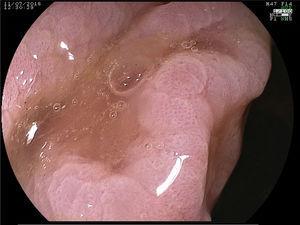

A 55-year-old man had unremarkable personal and family histories. Due to a positive fecal occult blood test, he underwent a video colonoscopy that identified multiple (more than 40) flat, elevated polyps (Paris classification 0-IIa) from 10 to 50mm in diameter, and predominating in the right colon (figs. 1 and 2). Magnification chromoendoscopy with acetic acid at 3% was performed (figs. 3 and 4), providing a better definition of the polyps. The anatomopathologic study of one of them reported serrated adenoma with no cytologic dysplasia (fig. 5).